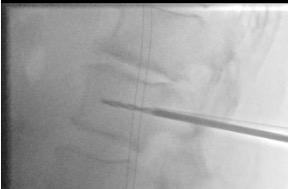

Bilateral pedicle entry

Create working channel

Insert balloons bilaterally